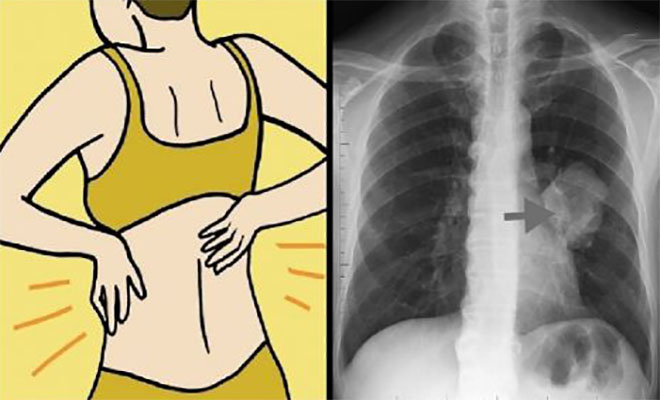

Οκτώ πρώιμα σημάδια του καρκίνου του πνεύμονα που κάθε γυναίκα πρέπει να γνωρίζει

Σημάδι # 4: Πόνος στους ώμους και στην πλάτη

Δεν θα σκεφτόσασταν ότι ο πόνος στην πλάτη σας θα συνδέονταν με τους πνεύμονές σας, αλλά για τις γυναίκες, οι απότομοι πόνοι και οι πόνοι στους ώμους μπορεί να δείχνουν ότι κάτι δεν πάει καλά. Αυτό συμβαίνει γιατί οι γυναίκες είναι πιο επιρρεπείς σε μια μορφή καρκίνου του πνεύμονα που ονομάζεται αδενοκαρκίνωμα. Οι όγκοι από αυτή τη μορφή καρκίνου αυξάνονται στα εξωτερικά στρώματα των πνευμόνων, έτσι μπορεί να ασκούν πίεση στην πλάτη και τη σπονδυλική στήλη.